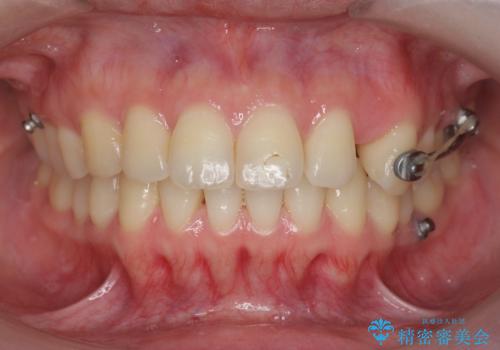

通常このような場合、抜歯してのワイヤー矯正治療も選択肢に入りますが、患者様の強い希望により抜歯を行わずマウスピースによる治療を選択しました。

カリエール・マイクロインプラントを用い、時間はかかりましたが大きく歯の後方移動が達成され、前歯の見た目が大きく改善されました。

大きな後方移動を達成するにはマイクロインプラントと日常的なゴムかけが大切です。